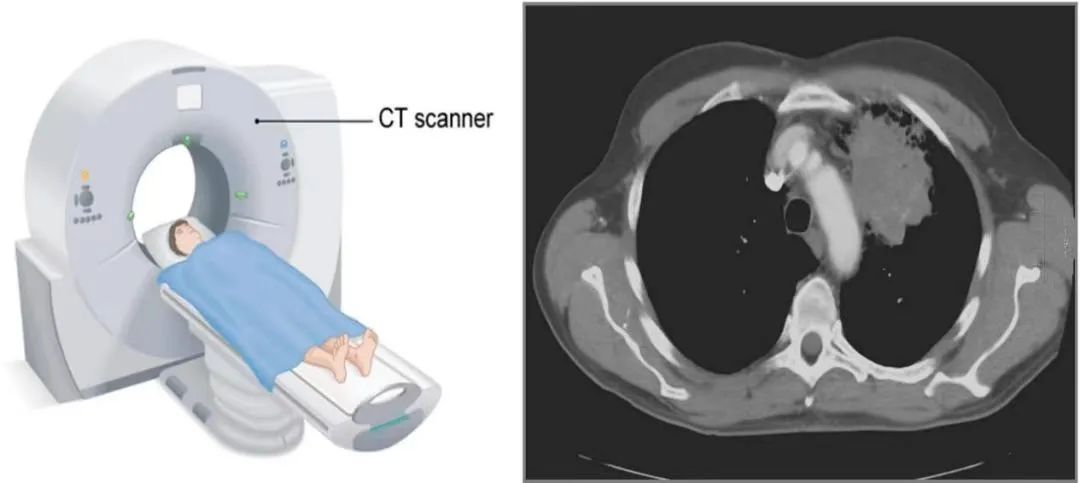

CT检查:CT即计算机断层扫描,它利用X射线旋转扫描人体,然后通过计算机处理生成三维图像。CT检查具有较高的分辨率,可以清晰地显示人体内部的组织结构,常用于肿瘤、脑血管病变等疾病的诊断。